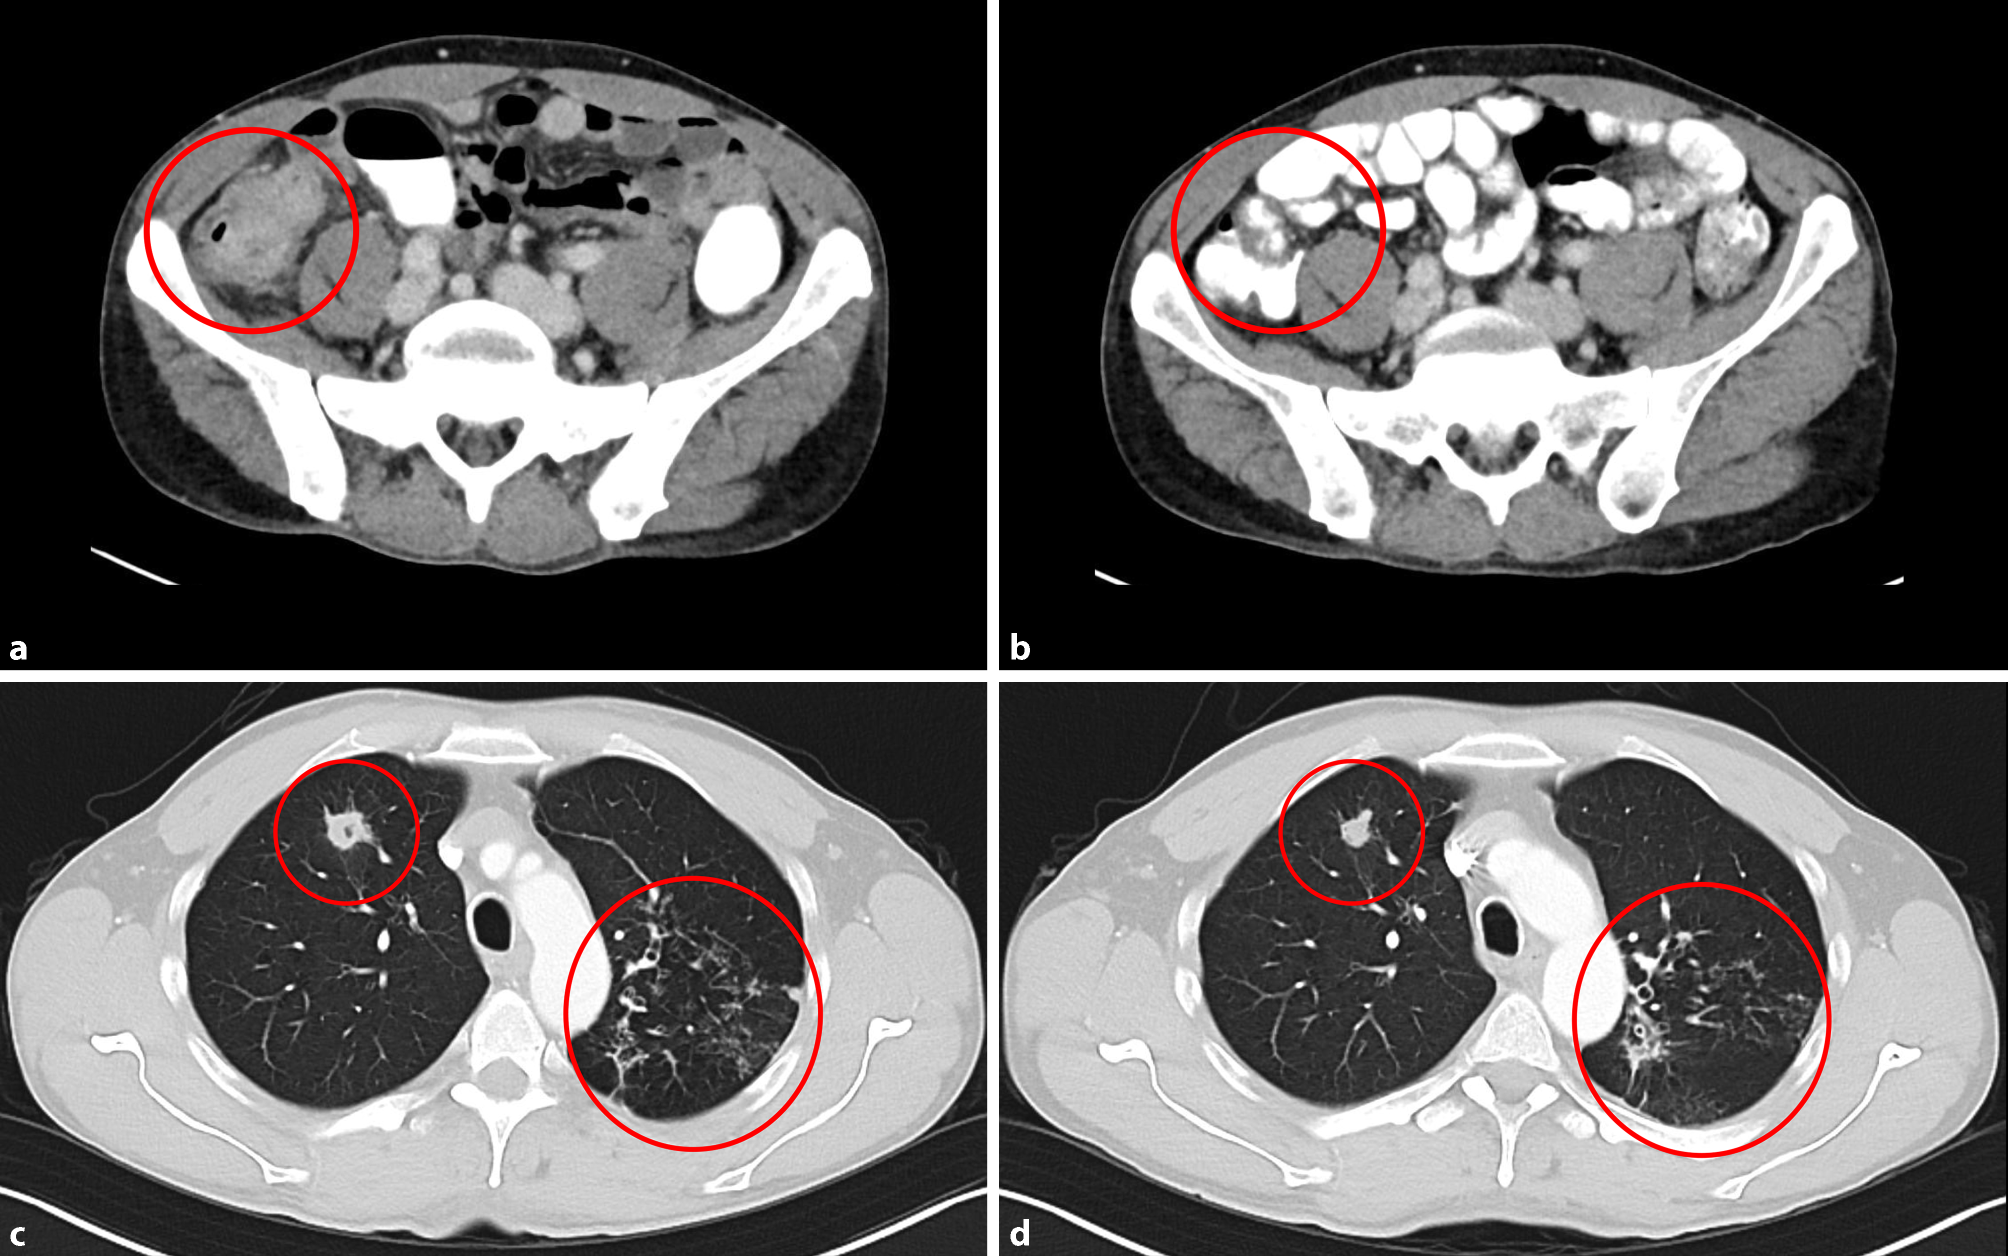

Computed tomography (CT) scan of the abdomen revealed marked thickening of the ascending colon wall with stenosis of the lumen and a retroperitoneal lymphadenopathy (Fig. 1a). For further investigation a colonoscopy was performed showing a tumor mass obstructing about 2/3 of the lumen of the cecum (Fig. 2). A biopsy was taken for histopathological evaluation. Gastrointestinal malignancy was suspected and the patient was subsequently registered for discussion in the interdisciplinary tumor board. Meanwhile, results of the histopathological evaluation revealed epithelioid granuloma with giant cells and surrounding inflammatory cells without any evidence of malignancy (Fig. 3). This finding was highly suspicious for M. tuberculosis infection.

Fig. 1

CT scan of the abdomen and the chest showing a gastrointestinal tumor mass in the cecum (red circle) and a pulmonary nodule in the left upper lung lobe as well as infiltrates in the right upper lung lobe (red circles) at time of diagnosis (a,c) and after 3 months of antimycobacterial treatment, respectively (b,d)

Treatment was well tolerated without any adverse events. Therapeutic drug monitoring revealed a suboptimal maximal concentration (Cmax) of rifampicin with 4.4 mg/l two hours post-dose. Consequently rifampicin dose was increased to 1200 mg od resulting in a sufficient Cmax of 16.0 mg/l [13, 14]. On the first follow-up CT scan of the abdomen and chest 3 months after the start of antimycobacterial therapy, improvement was documented showing a significantly shrinking intestinal tumor mass compared to initial findings (Fig. 1). Treatment with isoniazid and high-dose rifampicin was continued for another 7 months before TB treatment was stopped after a total of 12 months. At the end of treatment, the colonoscopy showed no pathological findings.